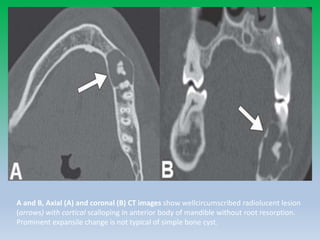

A and B, Axial (A) and coronal (B) CT images show wellcircumscribed radiolucent lesion

(arrows) with cortical scalloping in anterior body of mandible without root resorption.

Prominent expansile change is not typical of simple bone cyst.